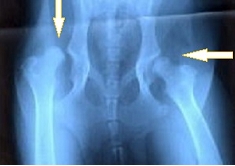

犬の股関節 (レントゲン画像)

正常な股関節

左右対称で

寛骨臼内に大腿骨頭が正しく収まっている

股関節形成不全症

寛骨臼が不完全で

大腿骨頭が収まっていない

片方は寛骨臼が無く

大腿骨頭が飛びだしている